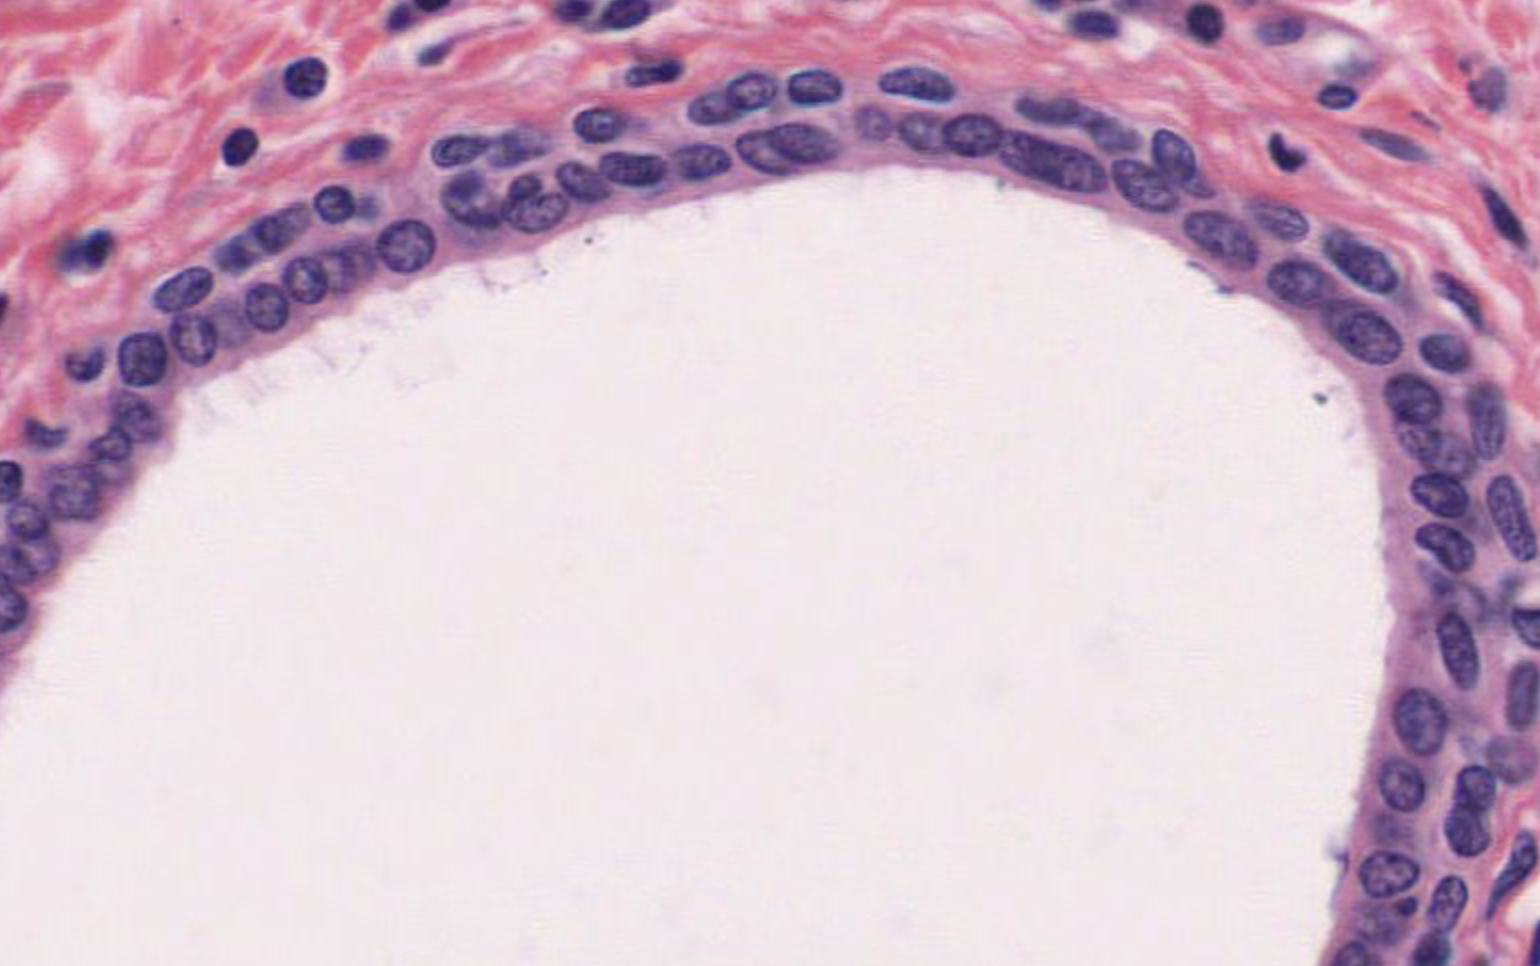

Tissue: nonkeratinized stratified squamous epithelium

Location: anterior surface of cornea

Function:

• protects underlying tissues in areas subject to ABRASION

• surface is exposed to air and is non-keratinized, the epithelium must be kept constantly moist with tears.